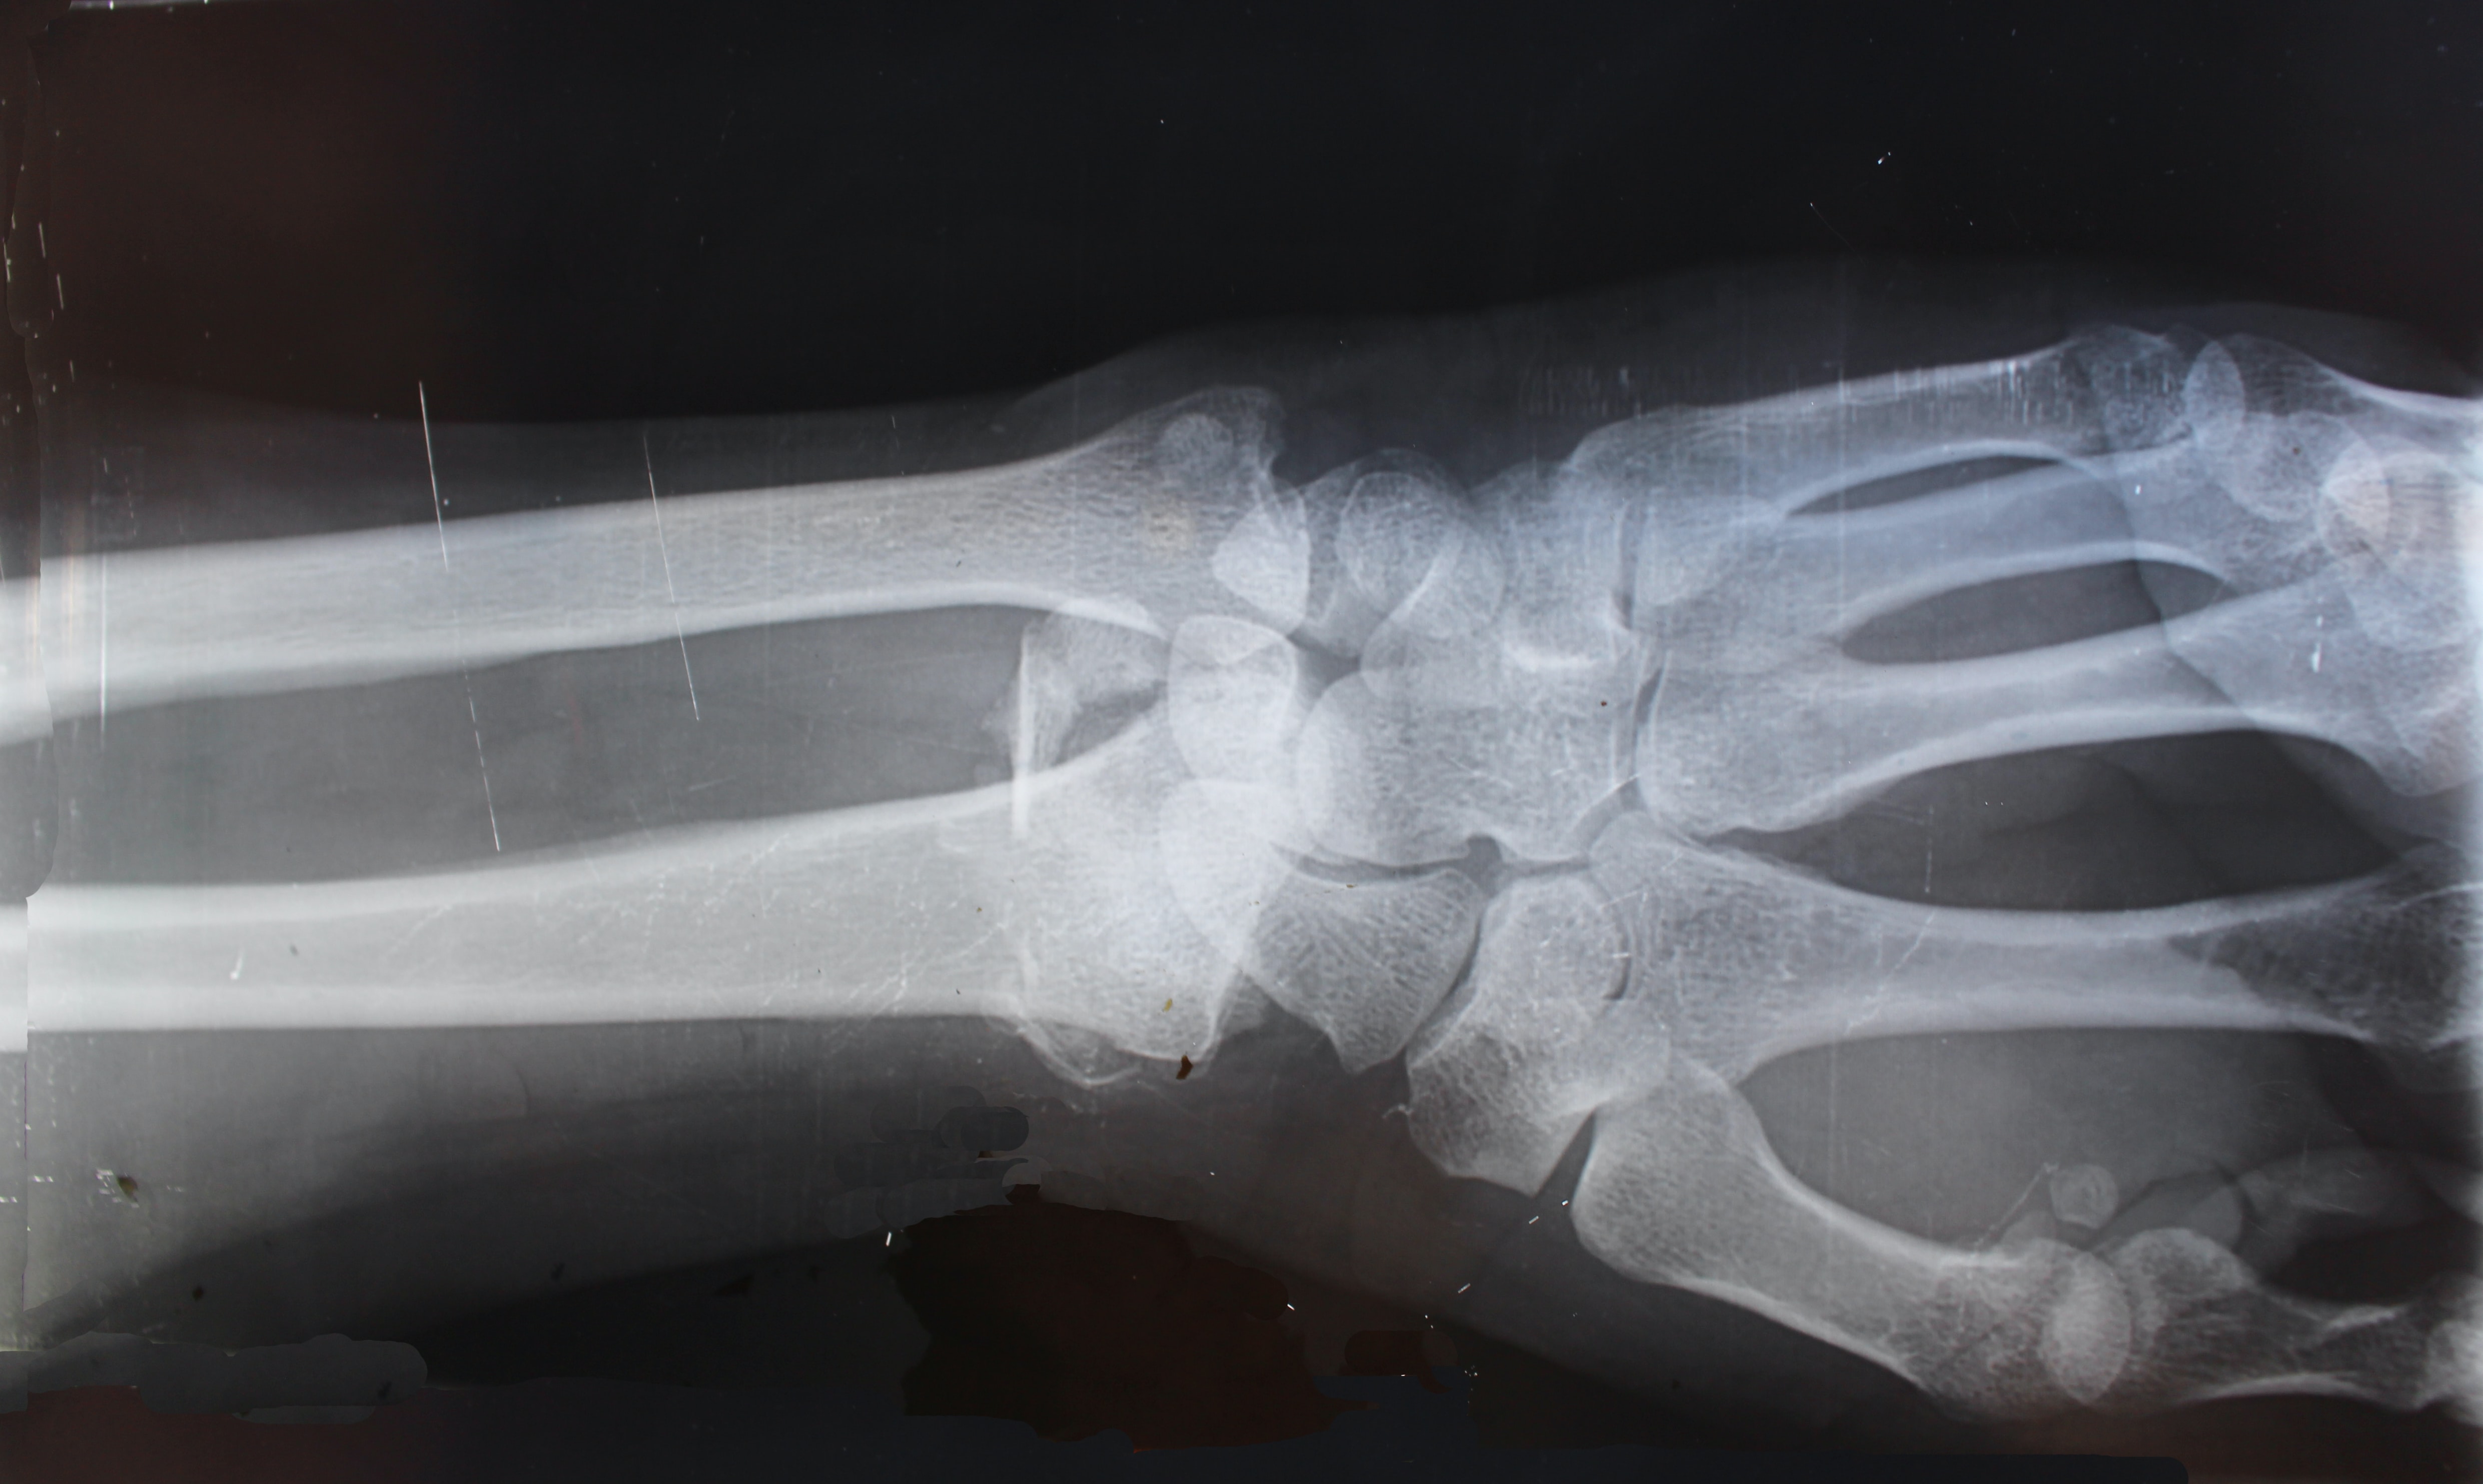

골관절염 치료방법

골관절염은 수일 통증이 느껴지는 경우 정형외과 엑스레이 촬영으로 쉽게 진단받을 수 있습니다. 엑스레이에서 확인이 되더라고 다른 질환으로 인해 증상이 유발된 것은 아닌지 확인이 필요합니다. 이러한 경우 관절에 찬 물을 추출해 검사하거나 피 검사를 진행하기도 합니다.